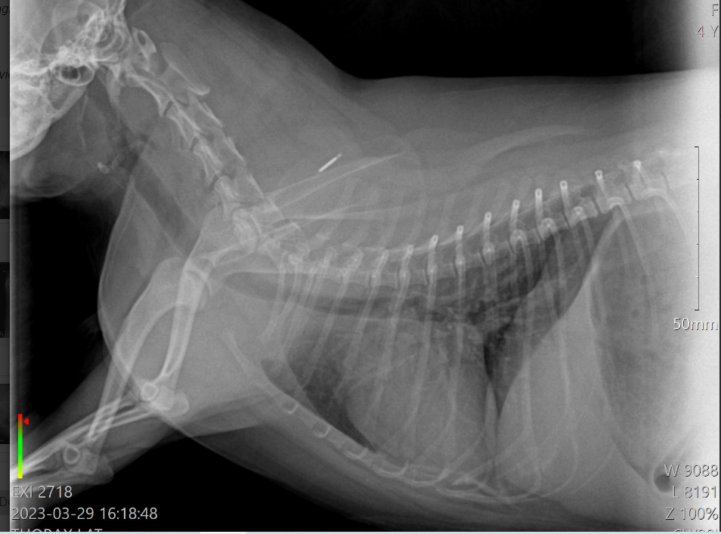

Chronic Cough problem with underline heart disease?

i upload this post in order to discuss one of my cases with you

Its about a yorkshire terrier, 3 years old, female, sterilised, that has coughing problems for 6 months. According with the owner, the problem didnt start 6 months ago, but earlier. But the last 6 months is really getting worse. Before it was once per week…